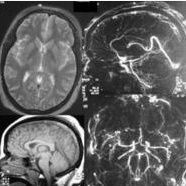

2.CT檢查

可以明確腦損傷的部位和範圍,了解有無繼發顱內血腫,並能對異物或骨片的位置、分布做出精確的定位。對後期的腦積水、腦膿腫、腦穿通畸形及癲癇病灶均有重要診斷價值。